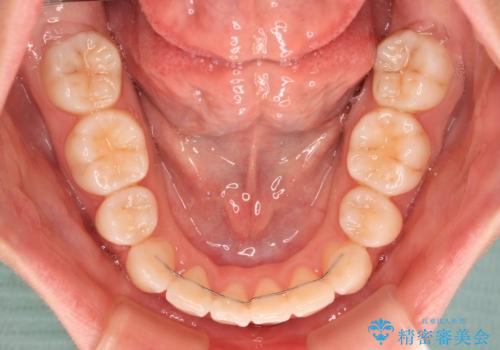

上下の骨格での左右差が小さかったことと、抜歯矯正であったことで、上下正中の位置をきれいに合わせることができました。